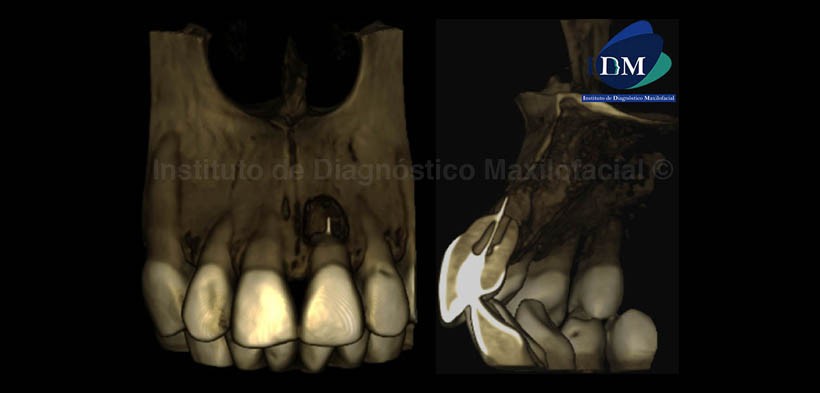

En la representación volumétrica (Fig.4), se observan los signos tomográficos mencionados desde una vista tridimensional.